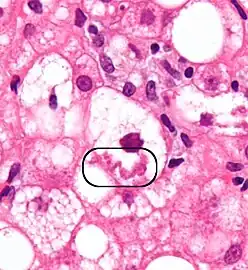

The primary characteristic of MASLD is the accumulation of lipids in the liver, largely in the form of triglycerides.[19] However, the mechanisms by which triglycerides accumulate and the reasons that accumulation can lead to liver dysfunction are complex and incompletely understood.[19][47][48] MASLD can include steatosis along with varied signs of liver injury: either lobular or portal inflammation (a form of liver injury) or ballooning degeneration. Similarly, NASH can include histological features such as portal inflammation, polymorphonuclear cell infiltrates, Mallory bodies, apoptotic bodies, clear vacuolated nuclei, microvesicular steatosis, megamitochondria, and perisinusoidal fibrosis.[16] Hepatocyte death via apoptosis or necroptosis is increased in MASH compared with simple steatosis, and inflammation is a hallmark of MASH.[32]

NASH (inflammation) and fibrosis stage 1

NASH (inflammation) and fibrosis stage 2

Lobular inflammation

NAFLD comprises two histological categories: NAFL, and the more aggressive form NASH. The presence of at least 5% fatty liver is common to both NAFL and NASH, but the features of substantial lobular inflammation and hepatocyte injuries such as ballooning or Mallory hyaline only occur in NASH. The majority of NAFL cases show minimal or no inflammation.[3][5][7] Pericentral and perisinusoidal fibrosis occur more often in adult-onset NASH, whereas portal fibrosis is more common in children with the disorder. NASH represents a more advanced stage of NAFL and is associated with poor outcomes such as cardiovascular events, cirrhosis, or hepatocellular carcinoma. ICD-11 does not use the term NAFL as it was deemed confusing with the family of disorders NAFLD. The preferred descriptions are instead: MAFLD without NASH or simple steatosis and "NASH". Also, the modifier with or without fibrosis or cirrhosis completes the diagnostic description.[3][7]